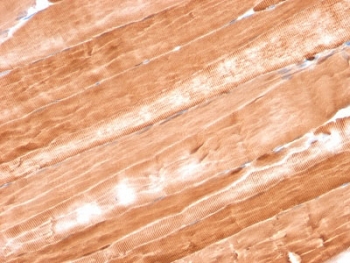

Product information "Anti-Myoglobin, clone MB/2105"

1 mg/ml in 1X PBS, BSA free, sodium azide free. Myoglobin is a cytosolic oxygen-binding protein responsible for the storage and diffusion of oxygen within myocytes. Expression of myoglobin is highest in skeletal and cardiac muscle. Myoglobin is well accepted as an O2-storage protein in muscle, capable of releasing O2 during periods of hypoxia or anoxia. In combination with other striated muscle markers such as vimentin and myogenin, myoglobin is helpful in the identification of rhabdomyosarcoma and tumors with skeletal muscle differentiation. Reportedly, myoglobin is expressed on epithelial cancer cells due to changed metabolic and environmental conditions. Protein function: Serves as a reserve supply of oxygen and facilitates the movement of oxygen within muscles. [The UniProt Consortium]

| Application: | IHC (paraffin) |